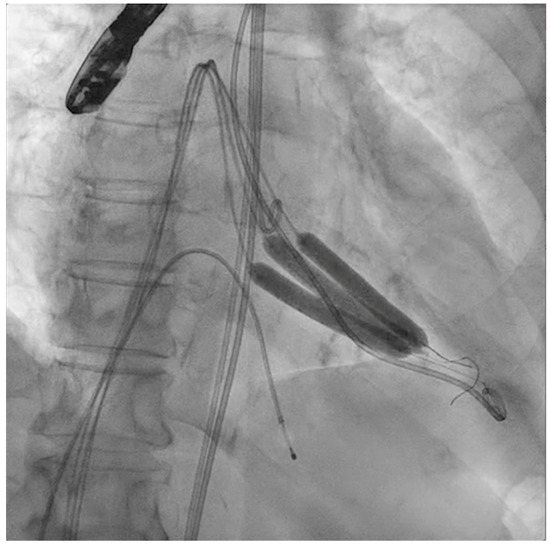

The next steps consist of crossing the mitral valve with three long high-support 0.014´´ wires downstream into the left ventricle (LV) (Figure 2) and then advancing three lithotripsy balloons (Shockwave Medical) across the mitral valve; with rapid pacing (120 beats/min), simultaneous inflations of all balloons will deliver a total of 90 pulses from each balloon (Figure 3). Finally, access to the LV has to be attained again with the Safari wire to complete PMC with large balloons appropriately sized to the mitral valve area and diameters (Figure 4). Embolic protection devices are encouraged to avoid neurological or systemic ischemic events due to calcific debris.

Figure 4.

Percutaneous mitral commissurotomy (non-compliant 26 mm balloon).